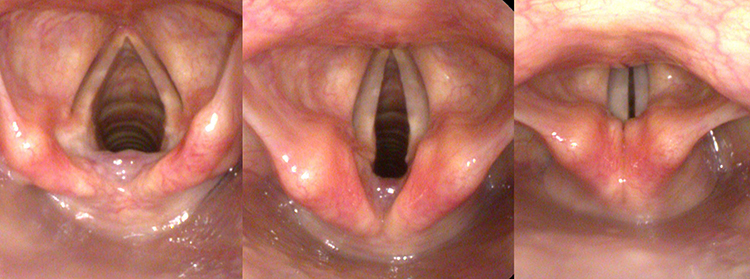

Где расположены и как выглядят

Связки расположены посередине гортани и покрыты слизистой оболочкой, которая имеет складчатую форму и, ihrerseits, покрыта многослойным плоским неороговевающим эпителием. Складки расположены таким образом, что между ними образуется пространство, называемое голосовым отверстием.

Когда мышечная ткань начинает двигаться, форма и размер щели изменяются в зависимости от амплитуды мышечной активности. Размер щели напрямую влияет на тон и частоту звуков, которые возникают.

Интересно, что размер щелей в гортани у мужчин и женщин существенно различается. Например, самая широкая щель в женской гортани окажется в сравнении равной по размеру самой узкой голосовой щели в мужской гортани. У мужчин гортань имеет острую и вытянутую форму, которая выступает наружу, образуя с внешней стороны кадык. Такая форма гортани определяет высоту мужского голоса.

В верхней части гортани находится овальное отверстие, известное как надгортанник, которое образуется подвижным гортанным хрящом. При глотании свободный край этого отверстия отклоняется назад, закрывая верхнее гортанное отверстие, а во время дыхания оно остается открытым. Этот процесс имеет важное значение для занятий вокалом.

В гортани человека находится два типа связок — две пары. Они представляют собой пару симметрично расположенных выступов, расположенных один над другим, с небольшими выемками между ними. Эти выступы известны как истинные и ложные голосовые складки.

- Настоящие складки представляют собой две симметрично расположенные образования из слизистого гортанного слоя. В них находятся мышечные скопления, расположенные в разных направлениях, что позволяет им двигаться не синхронно, а с разной интенсивностью и любой своей частью. Такое разнообразие мышечных движений обуславливает и разнообразие звуков, которые способен издавать человек. Помимо функции формирования звука, настоящие складки также выполняют защитную роль – смыкаясь полностью, они создают барьер, который не позволяет посторонним предметам проникать дальше в трахею.

- Ложные складки получили свое название из-за их нечетко выраженной функции. Они двигаются довольно медленно из-за слабо выраженной мышечной ткани. Однако они также участвуют в процессе звукообразования, хотя и не имеют возможности полного смыкания. Их работа наиболее заметна во время гортанного пения.

В ложных образованиях находятся железы, которые помогают увлажнять безжелезные истинные пары. Вся поверхность складок достаточно гибкая и подвижная. Внутри складок как с внешней, так и с внутренней стороны находятся щитовидно-грудные мышцы. Мышцы, находящиеся внутри, напрямую влияют на вокальные характеристики и, поэтому, называются вокальными мышцами.

Также здесь расположена голосовая мышца, которая активируется во время выдоха, начиная вибрировать, и помогает создавать звук.